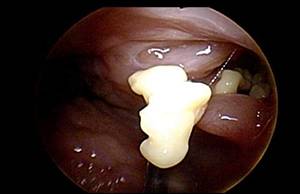

편도결석은 편도에 음식물 찌꺼기가 쌓여 생긴 결석을 말한다. 편도에는 편도음와라는 작고 깊은 구멍이 있는데, 음식물 등 노폐물과 세균이 뭉쳐 지독한 악취를 일으킨다. 편도결석은 몸에 생기는 다른 결석과 달리 말랑말랑하고 크기는 0.5mm 정도로 작다. 마치 쌀알 같은 생김새를 띤다. 편도결석이 있으면 목에 이물감이 들고 음식을 삼킬 때마다 불편하다. 그러나 이런 자각 증상 없이 입에서 악취만 나는 경우가 많다. 생선 비린내나 달걀 썩는 듯한 냄새가 나고 양치를 해도 쉽게 사라지지 않는다. 입을 크게 벌리면 편도 안쪽에 낀 결석이 보이기도 하나, 대부분 깊숙이 있어 보이지 않는다.

편도결석이 보인다고 해서 혼자 이를 면봉·젓가락 등으로 일부러 빼내면 안 된다. 빼내는 과정에서 편도를 자극해 상처·염증이 생길 수 있고, 오히려 편도음와가 점점 커져 결석이 쉽게 재발하기 때문이다. 편도결석이 의심될 땐 이비인후과를 찾아 전문적으로 이를 제거하는 게 안전하다. 병원에서는 후두 내시경을 통해 기계로 결석을 압출하는 치료를 한다. 결석이 너무 자주 재발하거나, 이로 인해 일상생활이 불편하다면 편도를 절제하는 수술을 하기도 한다. 편도결석을 예방하기 위해선 평소 편도에 염증이 생겼을 때 즉시 치료해야 한다. 입이 마르지 않도록 물을 자주 마시고 양치질을 깨끗이 해 음식물이 끼지 않도록 하는 것도 도움이 된다.